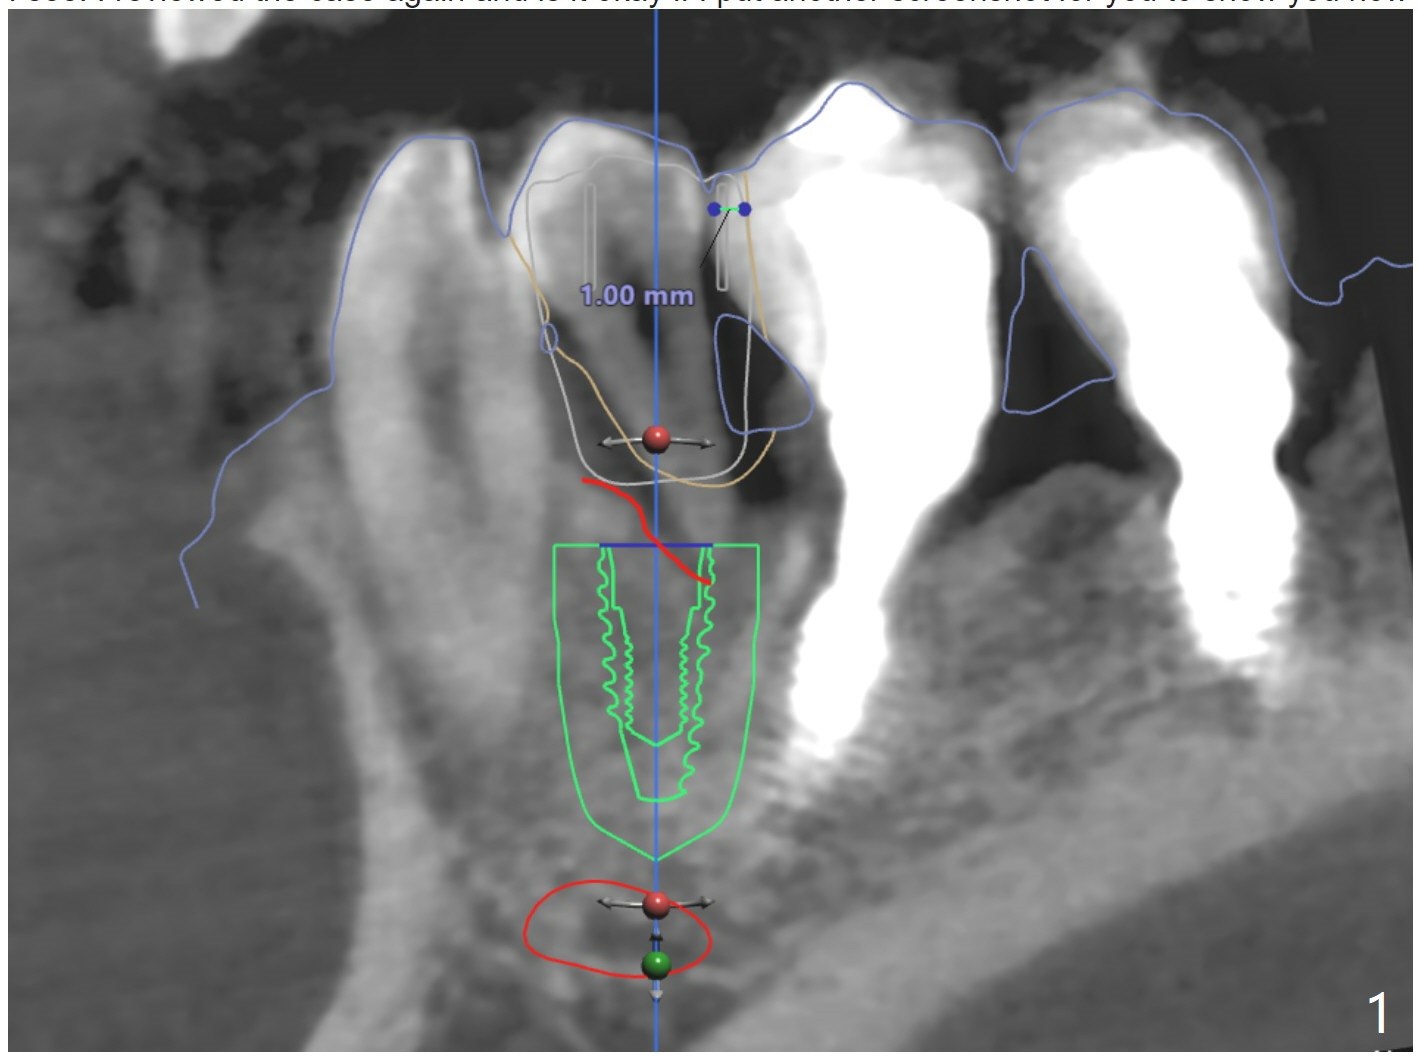

I am guessing the reason of the deviation would be the slanted surface of the bone. And when you see the red marked site (Fig.3), that shows white color (which also means dense bone). If there was more space, we could've used a regular metal sleeve and plan for a bone trimmer prior to the initial drilling, but this case, we couldn't do that. Narrow metal sleeve was used with 12mm of max offset. So, in this kind of case, I am sorry to tell you but we might have to manually remove the excessive bone to flatten the bone surface for osteotomy before implant placement when the regular bone trimmer can not be used.